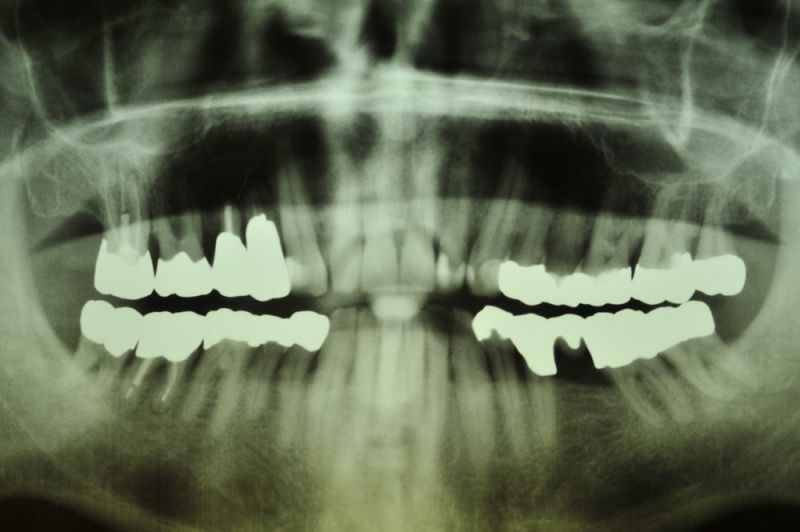

Vor ca. 20 Jahren wurde der Patient umfassend funktionstherapeutisch versorgt. Bereits zum damaligen Zeitpunkt waren die Zähne des Patienten vorgeschädigt und es lag eine Parodontalerkrankung vor.

Der Patient wurde dann über etliche Jahre, was das Thema Parodontalrecall betrifft nicht ganz optimal betreut, weil die berufliche Situation des Patienten das nicht zuließ.

In der Zwischenzeit sind vorgeschädigte Zähne verloren gegangen und wurden zum Teil durch Implantate ersetzt.